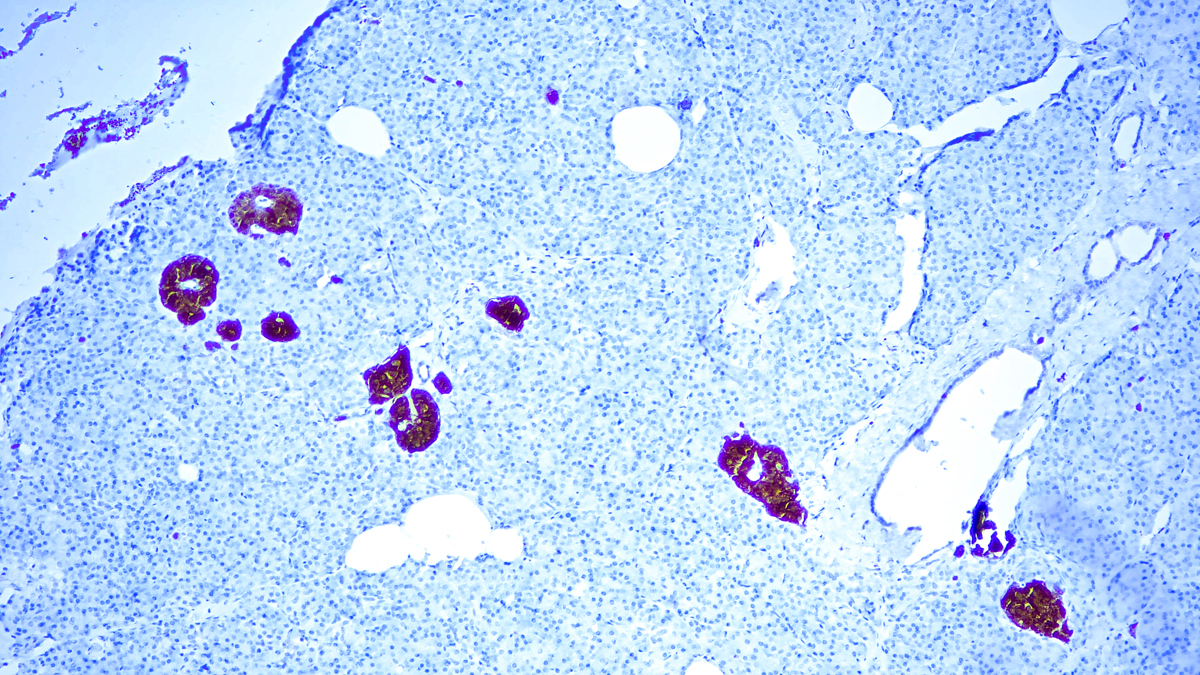

Three isoenzymes of enolases are identified, alpha, beta and gamma. Alphaisoform is expressed in most tissues, whereas beta-form is expressed predominantly in muscle tissue whereas gamma-enolase is found only in nervous tissue. These isoforms exist as both homodimers and heterodimers, and they play a role in converting phosphoglyceric acid to phosphenolpyruvic acid in the glycolytic pathway. NSE-gamma is a useful marker to identify peripheral nerves and tumors of neuro-endocrine origins, such as pheochromocytomas. It is usually employed in combination with other markers such as Synaptophysin, Chromogranin A, and Neurofilament.

| Positive Control Tissue | Pancreas, Cerebellum, Pheochromocytoma |